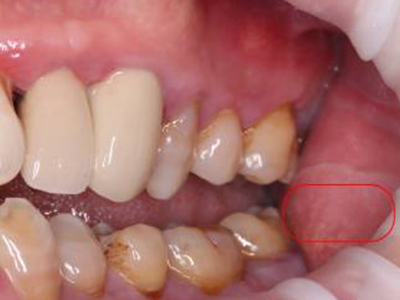

异位皮脂腺又称Fordyce病、皮脂腺异位症,为皮脂腺异位而形成,表现为黏膜上出现高于黏膜面的白色或淡黄色斑点或稍隆起的扁平斑丘疹,可聚集呈斑块样。本病以两颊黏膜及唇部黏膜多见,也可发生于外阴部位,多于青春期或青春期后发生。

异位皮脂腺常发生在口腔颊黏膜以及下唇、上唇,牙龈黏膜少见,也可发生在男女阴部黏膜及肛周,偶尔见于乳晕及眼睑。女性常见于小阴唇内侧面,多对称分布,少数在大阴唇内侧面;男性见于龟头,也可见于包皮内侧面。

皮疹为针头至粟粒大小,白色、淡黄色或黄色小斑点,或稍隆起的扁平斑丘疹,可聚集呈斑块样。当黏膜被拉紧时,皮疹表现得更明显(实际上小丘疹在黏膜内)。皮疹一般不融合,挤压皮疹并无内容物排出,有自愈的倾向,偶尔有瘙痒感或灼热感。